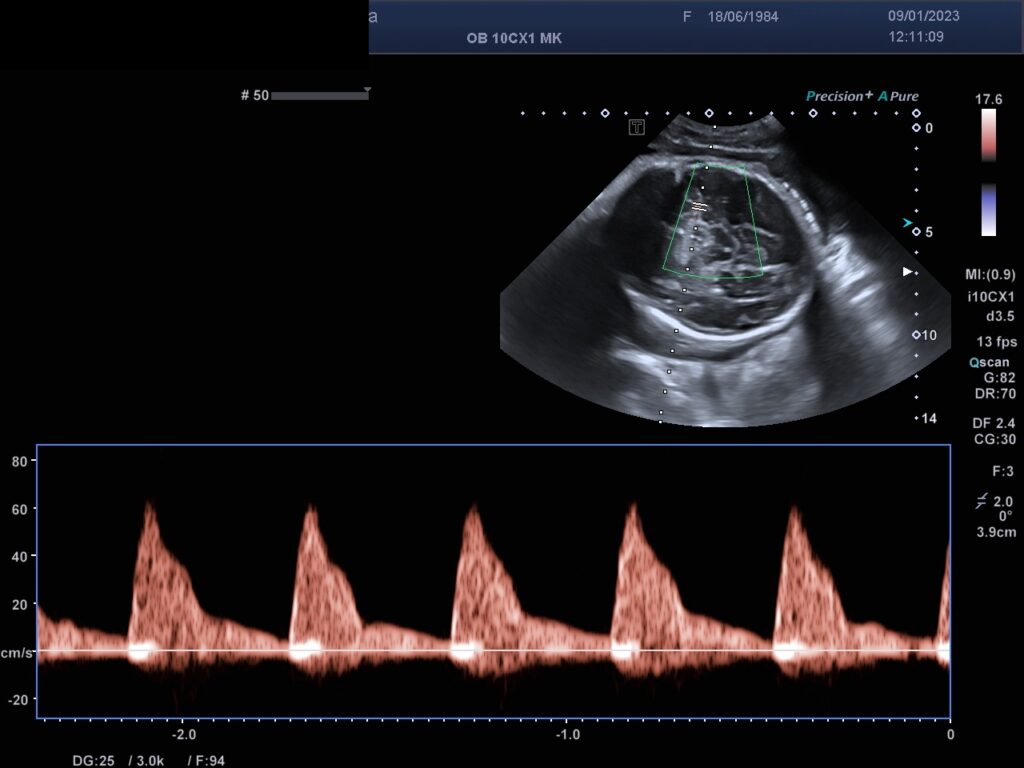

Farb-/ und Spektraldopplersonographie

Mit der Farbdopplersonographie können fetale und mütterliche Gefäße dargestellt werden und dann Spektraldopplerkurven erstellt werden, die semiquantitativ mittels Indices auswertet werden . Damit ist eine Zustandsbeurteilung des Feten als auch der Durchblutungsverhältnisse der Gebärmutterarterien der Schwangeren möglich.

Die Farb-/ und Spektraldopplersonographie ermöglicht die Zustandsbeurteilung des Feten.